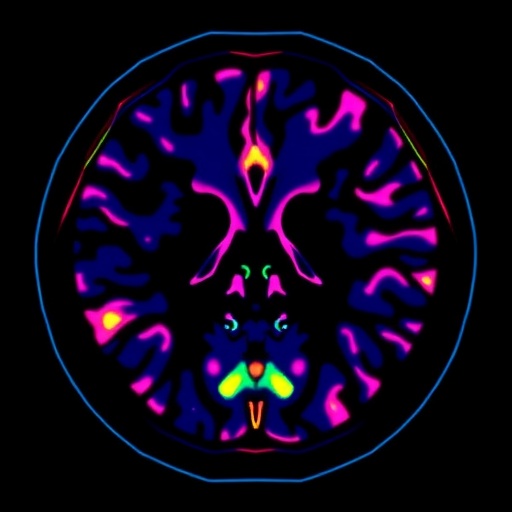

The implications of this AI advancement extend beyond breast imaging. The methodology of combining interpretability with clinical-grade performance could serve as a blueprint for other medical imaging domains where false-positive rates are high. Radiological disciplines such as prostate MRI, lung nodule detection, and brain tumor classification stand to benefit from similar AI-enhanced stratification techniques, promising a broader impact on diagnostic precision and patient care standards.